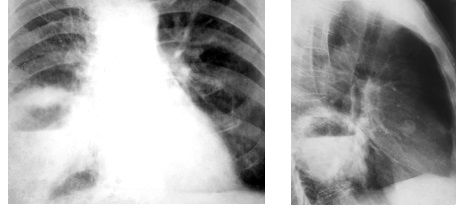

Рис. 2. Рентгенограмма органов грудной полости в прямой проекции. Слева на всем протяжении легочного поля – просветление.

Рис. 3. Рентгенограмма органов грудной полости в прямой проекции. Слева в среднем легочном поле большое затемнение округлой формы.

Распространенное просветление встречается при пневмотораксе (рис 2). При этом, как правило, в медиальных отделах видим коллабированное легкое, смещение средостения в противоположный бок, а размещение газа не соответствует долевому строению легкого.